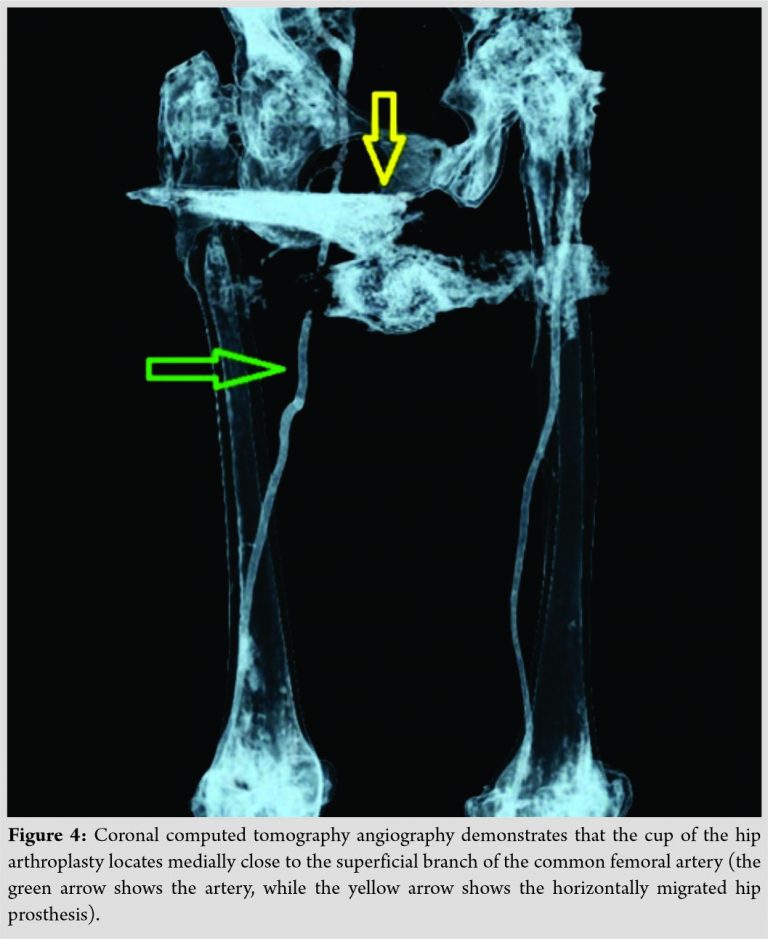

A computed tomography (CT) scan and a CT-angiography were performed, to evaluate the exact location of the migrated THA components and any proximity of them to the great leg vessels. CT scan disclosed that the stem and cup were located on the floor of the adductor femoral muscles, subcutaneously close to the medial third of the groin area. The proximal one-third of the femur was perforated by the stem in both medial and lateral cortices (Fig. 3).

CT angiography revealed the proximity of the screw socket to the superficial branch of the common femoral artery (Fig. 4).